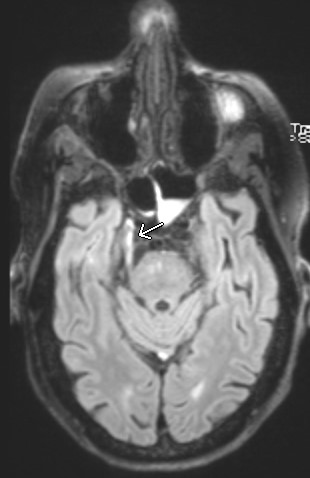

I have seen cranial neuropathy missed often enough that I'd like to remind everyone that every brain MRI is also a cranial nerve MRI. Case: multiple lung cancer metastases status post Gamma Knife SRS, with "right sided headache, eval for new mets". #RadEd #HNRad #Neurorad

Case: multiple lung cancer metastases status post Gamma Knife SRS, with "right sided headache, eval for new mets".  #RadEd #HNRad #Neurorad